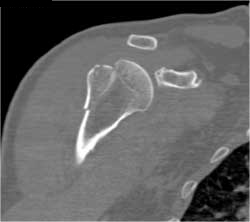

Diagnosis

Prior Bone Resection